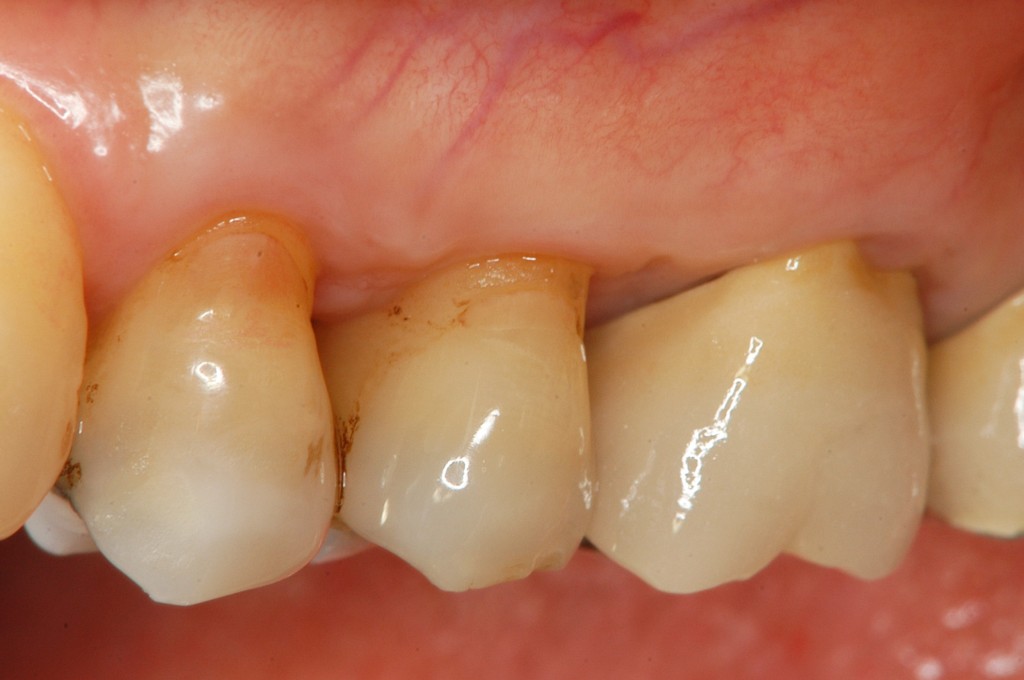

• 治療前

歯茎が下がってきた。歯茎がやせてきて気になる。歯周病かどうか心配。このままどんどん歯茎がやせてしまって,歯が抜けるのではないかと不安。

上の奥歯の歯茎がやせていて,根っこが見えている状態です。治療法はエムドゲインと結合組織移植を用いた根面被覆術を選択しました。